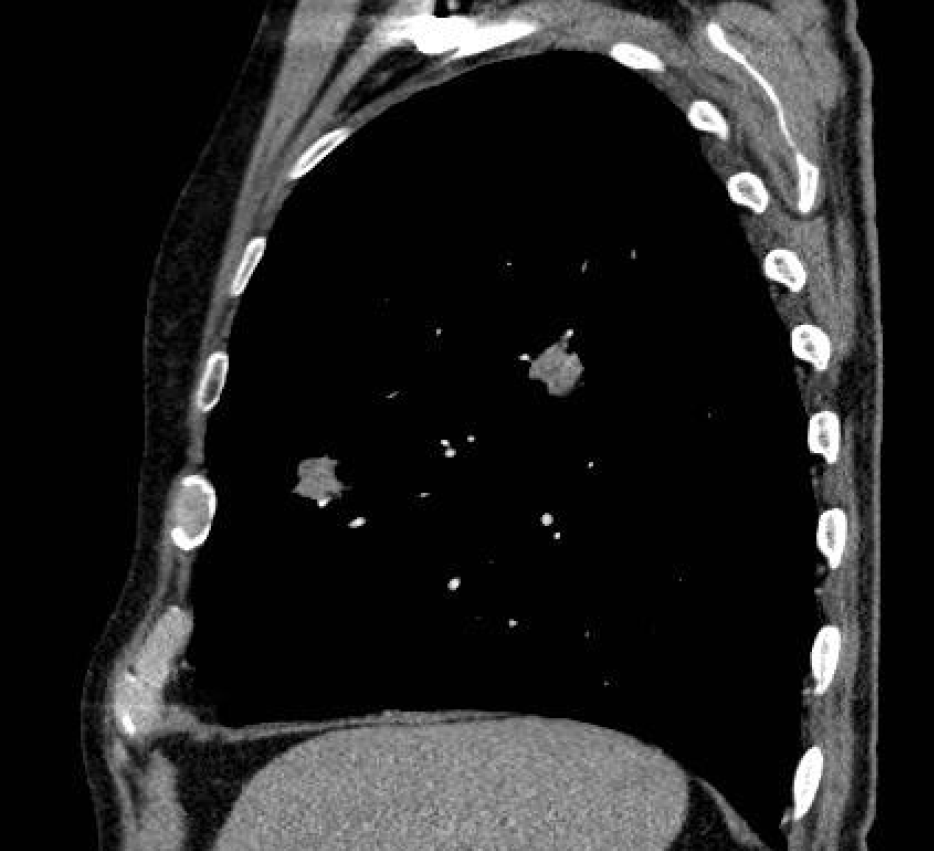

Solitary pulmonary nodules are an increasing diagnostic problem. Multiple approaches may be undertaken to establish a tissue diagnosis, including sputum cytology, percutaneous image-guided aspiration/biopsy, and bronchoscopic sampling. To obtain tissue samples for the histological evaluation of peripheral lesions, bronchoscopy under fluoroscopy is the standard procedure. This demands expensive x-ray equipment in the bronchoscopy suite or coordination with the radiology department and causes exposure to radiation for patient and staff. An important factor affecting the yield is that lesions situated beyond the airway lumen are not visible to the bonchoscopist, resulting in ‘blind’ biopsies. Fluoroscopy offers some assistance for localizing such lesions, especially in lesions larger than 3 cm. The two-dimensional projection views produced by fluoroscopy often do not show smaller lesions. In such lesions, mostly peripheral pulmonary lesions not visible endobronchially, diagnostic yield of routine bronchoscopy may therefore be less than 20%. The highest diagnostic yield for bronchoscopic evaluation of small SPNs appears to be associated with the use of radial ultrasound miniature probes (EBUS) in the diagnostic procedure. EBUS miniature probes employ a flexible catheter, housing a mechanically rotated ultrasound transducer which produces a 360° radial ultrasound image. The technique to use a miniature probe to guide TBLB was first described by Herth (Herth et al, Endobronchial Ultrasound-Guided Transbronchial Lung Biopsy in Solitary Pulmonary Nodules and Peripheral Lesions, Eur Respir J., 2002, Oct; 20(4), pp 972- 974) passing the probe into the bronchial subsegments until the characteristic ultrasound signal of a solid lesion is displayed. Numerous groups have published their experience with EBUS-guided evaluation of SPNs since.

A recent procedural improvement was achieved with the introduction of a guide sheath as an accessory to the EBUS probe. The sheath acts like a prolonged working channel of the bronchoscope and allows the removal of the probe after visualization of the solid lesion. With the distal end of the guide sheath still at the target site, sampling devices can then be brought forward. Specimens from four to six biopsies shall then be obtained through the guide sheath using regular biopsy forceps. Unfortunately the EBUS probes are not steerable. Therefore, navigation support (based on a virtual bronchoscopy calculated on CT data) is helpful to guide a thin bronchoscope close to the lesion. As the navigation systems lack the function to directly visualize the lesion, EBUS miniature probes should be used to confirm the location of the lesion before biopsy. Here, combining EBUS and navigation bronchoscopy improves the diagnostic yield of flexible bronchoscopy in peripheral lung lesions without compromising safety. This has been demonstrated for electromagnetic navigation bronchoscopy (ENB) by Eberhardt (Eberhardt et al., Multimodality Bronchoscopic Diagnosis of Peripheral Lung Lesions, Am J Respir Crit Care Med, 2007, Vol 176. pp 36-41) proving highest diagnostic result when combining ENB and EBUS. Recently it was also demonstrated by Asano and colleagues that virtual bronchoscopy combined with EBUS increases diagnostic yield (Asano et al., Virtual Bronchoscopic Navigation Combined with Endobronchial Ultrasound to Diagnose Small Peripheral Pulmonary Lesions, Thorax, published online July 11, 2011, doi: 10.1136/thx.2010.145490).